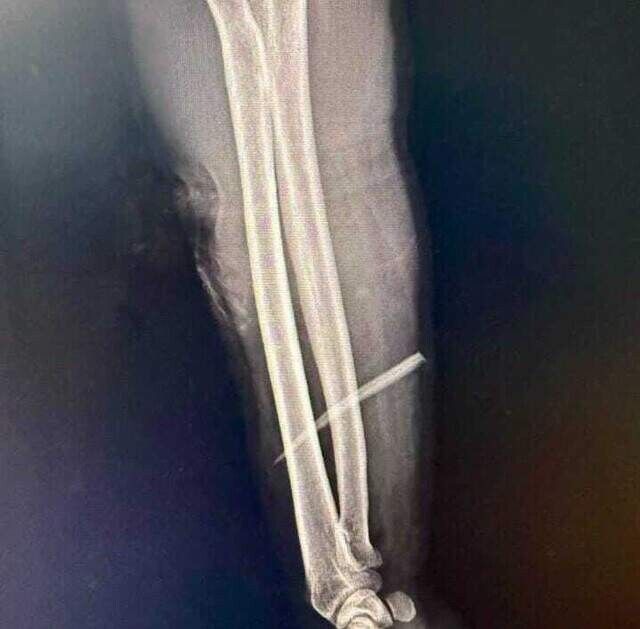

Erasmo Luiz Portilho, de 46 anos, foi pescar no rio Aquidauana, em Camisão, na noite de quarta-feira (10) e acabou atingido pelo ferrão de um peixe. O pescador está internado há três dias com o ferrão cravado no braço e corre risco de perder o membro. A cirurgia para a retirada está marcada para as 15h desta sexta-feira (12).

“Faz três dias com o ferrão do pintado lá no braço. Agora diz que vai operar às 15h. Estamos na expectativa. Mesmo com a operação, vamos precisar esperar abrir a região para ver se não afetou nenhum nervo e aí ver se vai conseguir voltar ao normal. Como ele perdeu muito sangue no local onde aconteceu o acidente, se demorasse, ele nem chegava. Praticamente nasceu de novo”, relatou o jovem.